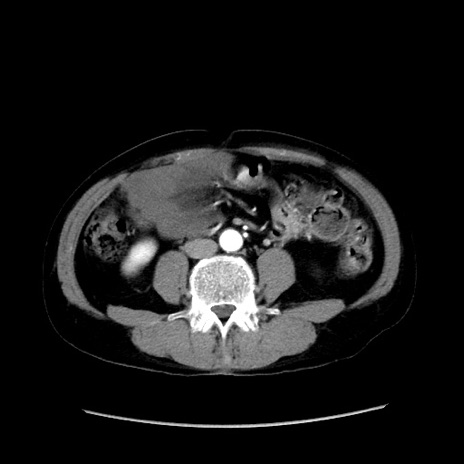

症例37(横断像)

【症例】40歳代 男性

【主訴】腹痛

【現病歴】4時間ほど前に電車に乗車中に臍部上より腹痛出現。徐々に増悪し起立困難となり、救急外来受診。生ものは数日食べていない。今朝お雑煮を食べた。

【身体所見】BT 36.8℃、BP 117/84mmHg、HR 91/min、SpO2 97%、苦悶様、腹部:臍上部広範囲圧痛あり、反跳痛±

【データ】WBC 8100、CRP 0.03